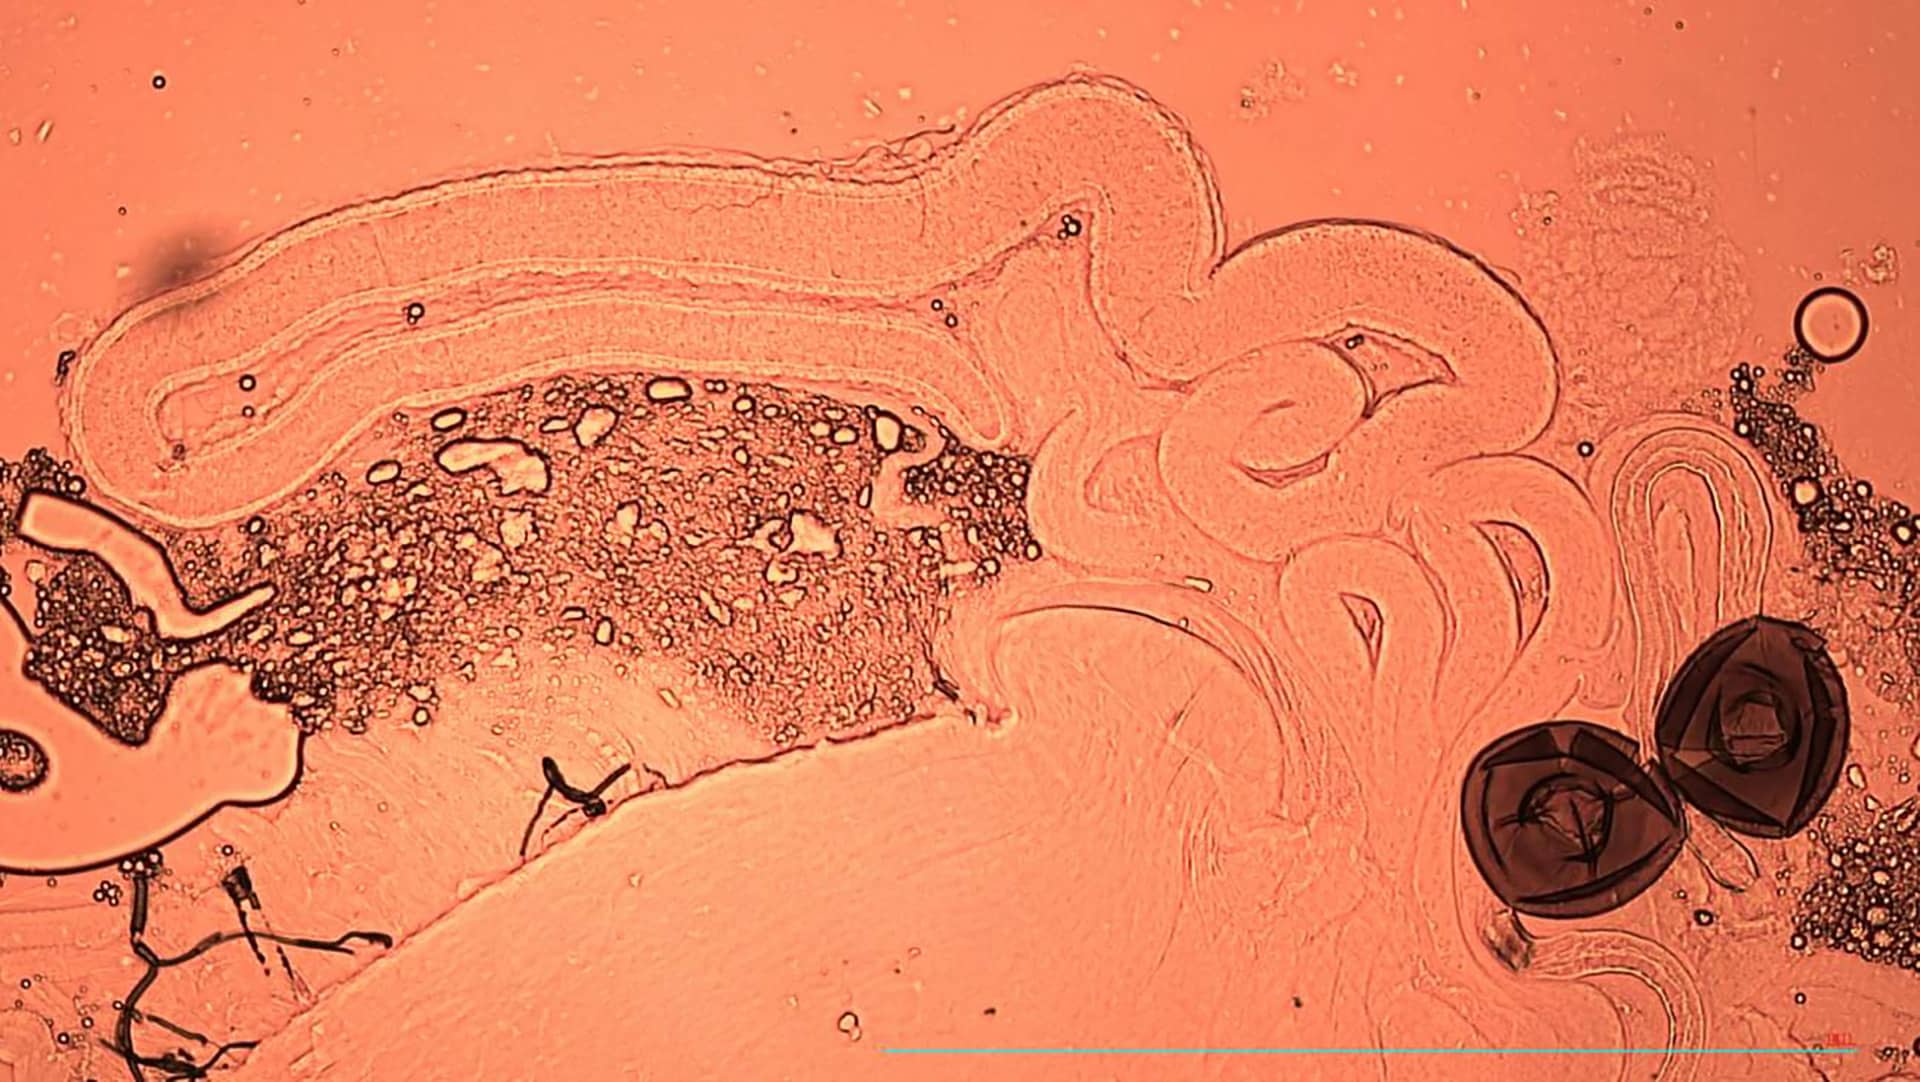

Los espermatozoides tienen un citoplasma muy limitado, por lo que agotan rápidamente sus reservas de energía y su capacidad de reparación. Esto genera mayor estrés oxidativo y daños genéticos cuando permanecen almacenados. “Los hombres necesitan la eyaculación para expulsar el semen dañado. Así obtienen espermatozoides nuevos y más frescos para la próxima vez”, explicó Krish Sanghvi en declaraciones recogidas por la agencia SINC.